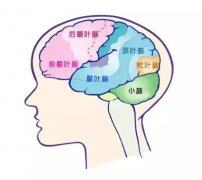

厚朴方舟是专业的出国看病医疗服务机构,为患者整合美国日本及国外脑膜瘤治疗权威的排名靠前的医院和专家资源。结合患者的病情,对患者病情进行诊断,分期治疗方案。对患者提供脑膜瘤相关疾病出国治疗申请服务、新的治疗方法技术、治疗药品药物等相关知识。

脑膜瘤患者或者关注脑膜瘤相关知识的人群会遇到一个词叫小脑膜瘤,厚朴方舟医学顾问今天为大家科普一些与小脑膜瘤有关的内容,包括小脑膜瘤是什么?小脑膜瘤治疗方案等内容,一起看看

脑膜瘤后遗症一般包括:突眼、眼睑下垂、头痛、记忆力减退等等,严重的则可能出现瘫痪、脑疝等,有可能会危机生命,因此,脑膜瘤后遗症治疗十分重要,那么脑膜瘤后遗症怎么进行治疗